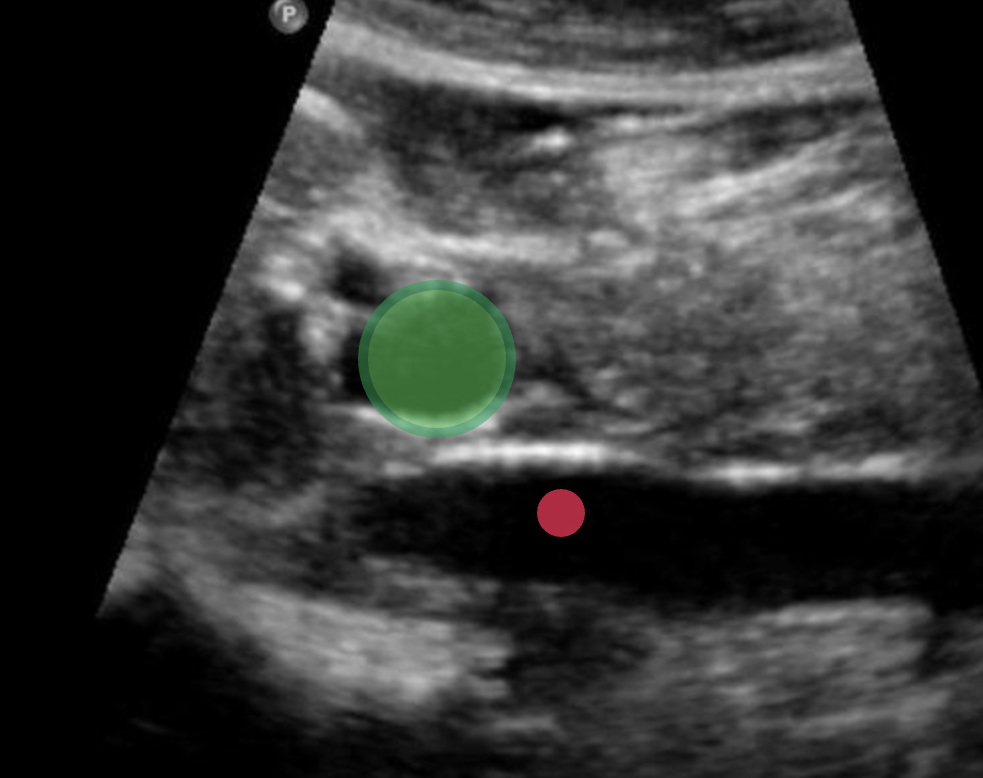

Use your mouse to place your cursor over the center of the lateral left lobe of the liver and click to mark the structure

Use your mouse to place your cursor over the ligamentum venosum and click to mark the structure.

Use your mouse to place your cursor over the main lobar fissure and click to mark the structure.

Use your mouse to place your cursor over the left portal vein and click to mark the structure.

Use your mouse to place your cursor over the main portal vein and click to mark the vessel.

Use your mouse to place your cursor over the hepatic artery and click to mark the vessel.

Use your mouse to place your cursor over the main portal vein and click to mark the vessel.

Use your mouse to place your cursor over the left medial superior segment of the liver and click to mark the structure.